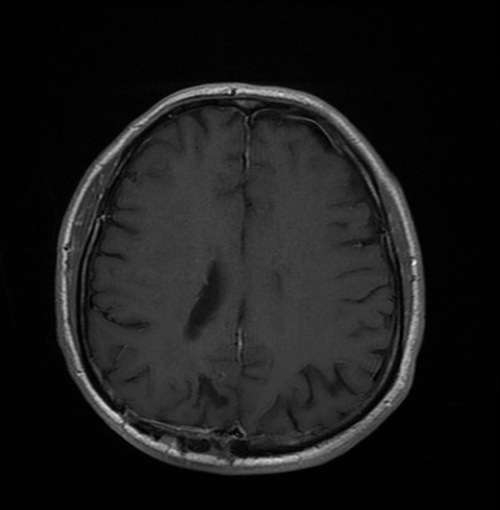

Bazı vakalarda tümör çıkartılamaz. Böyle durumlarda cerrah sadece biyopsi yapar ve tümörün küçük bir kısmını çıkartır. Çıkan kısım patolojiye yollanır ve mikroskop altında incelenerek kesin tipi öğrenilir. Bu tedavinin şekillendirilmesinde önemli bir bilgi kaynağıdır. Biyopsi açık cerrahi ile yapılabildiği gibi genel durumu buna izin vermeyen hastalarda özel sistemler kullanılarak bir iğneyle de yapılabilir. Doktor hastanın başına özel bir çerçeve (Frame) takarak MR ve/veya BT görüntüleri alır. Bu şekilde tümör dokusunun kafa içindeki kesin yerleşim yeri koordinatları ile belirlenir. Bu bilgilerle kafa tasına küçük bir delik açılarak biyopsi iğnesi doğrudan tümöre hedeflenir ve biyopsi alınır. Bu tekniğe stereotaksi denilir.

Bu tedavi şekillerinden birisi ile tedavisi yapılan hastalar, süresi doktorlar tarafından belirlenen ve ilk başlarda daha sık; sonra araları açılan kontrollere gelirler. Kontroller sırasında BT veya MR görüntüleri ile tümördeki değişimler takip edilir, hastaların tam bir muayenesi yapılır. Gerek görülürse ilaç tedavileri düzenlenir.